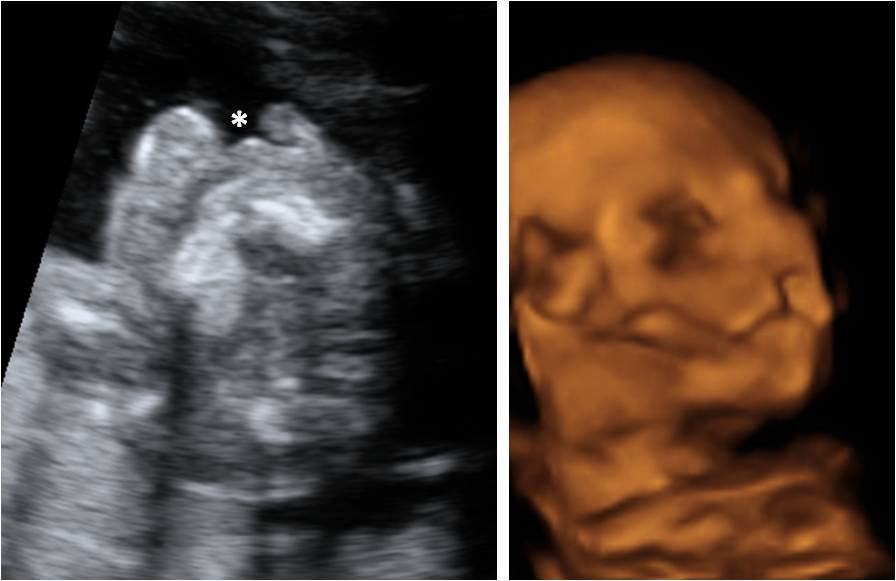

En la ecografía en 2D de la semana 20 de embarazo se hace un estudio pormenorizado de los órganos internos del feto y de su anatomía. Así se descubren muchas malformaciones congénitas, como en este caso, un pie equinovaro o zambo.

Imagen ecográfica de pie zambo o equinovaro

En la imagen superior se ven los dos pies de un feto, en el lado izquierdo un pie bien orientado con la pierna y en el lado derecho un pie con una desviación anómala, denominada pie equinovaro o zambo.